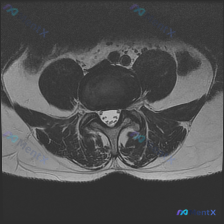

刚整理了一份很有警示意义的读片病例,分享给大家,这个坑平时读片真的很容易踩。 病例基本信息 临床诉求:患者因腰痛就诊,临床怀疑椎间盘病变,提供一张腰椎MRI T2加权轴位影像请读片。 影像基础评估 这是一张腰椎横断面(轴位)T2加权影像,清晰度和信噪比都不错,没有明显运动伪影,可以清楚辨认椎体、椎弓...

刚整理了一份腰椎MRI读片病例,只有单张轴位T2加权图像,把完整的分析思路整理出来和大家分享。 一、影像基本信息 这是一张腰椎MRI轴位T2加权图像,清晰度良好,解剖结构辨识度高: - 扫描水平为腰椎单个节段(大概率L4/5或L5/S1,具体需结合矢状位确认) - T2序列特征符合典型表现:脑脊液高...

整理了一份腰椎MRI读片讨论,给大家分享一下思路。 病例影像基础信息 本次仅提供放射影像-腰椎MRI-T2序列-轴位单张图像,扫描层面为腰椎某一节段,视觉判断符合腰4/5或腰5/骶1椎间盘水平,无临床病史、体征及其他检查资料,核心问题是明确该层面是否存在椎间盘病变相关影像学表现。 影像具体读片结果...

看到这张腰椎MRI-T2轴位影像,大家第一反应是什么?问题问的是椎间盘病变,整理一下分析思路和大家分享。 一、影像基本信息 这是腰椎椎间盘层面(最可能为L4/5或L5/S1)的T2轴位扫描,我们先梳理所有客观发现: 1. 椎间盘情况:中央区域信号较正常稍低,提示椎间盘脱水变性;但后缘形态完整,没有明...

看到这一份腰椎MRI读片病例,临床怀疑存在椎间盘病变,我们整理一下影像资料和完整分析思路,大家一起讨论。 病例影像资料 本次提供的是腰椎MRI T2序列轴位图像,分析如下: 1. 扫描层面:位于下腰椎节段,可清晰辨认中央的硬膜囊、马尾神经根,以及侧方的关节突关节、椎旁肌肉 2. 核心影像发现: -...

拿到这份资料:临床怀疑椎间盘病变,只提供了一张腰椎MRI T2加权轴位图像,我整理了分析思路跟大家分享。 先看这份影像本身的信息 这是腰椎L3/4或L4/5椎间盘水平的轴位片,影像可见: 1. 解剖结构:中央硬膜囊脑脊液信号正常,椎体后缘轮廓清晰,两侧关节突关节间隙对称,黄韧带无明显增厚钙化,椎旁软...

收到一份腰椎MRI单张轴位片,临床怀疑椎间盘病变,整理一下读片思路和分析,和大家交流。 一、影像基本信息 这是一张腰椎MRI T2加权轴位扫描图像,我们逐层拆解结构: 1. 椎体与终板:椎体后缘信号正常,低信号符合皮质骨表现,没有明显骨质破坏、水肿,也没有典型Modic终板炎改变 2. 椎间盘:髓核...